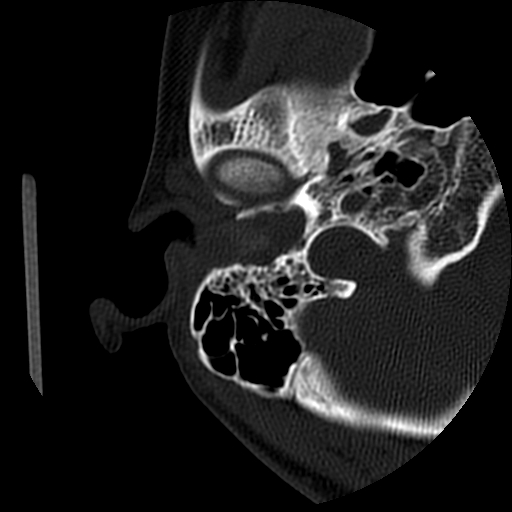

以下是引用随光逐影在2009-8-19 7:25:00的发言:[br]右侧慢性中耳乳突炎,右侧中耳腔及外耳道肉芽肿或胆脂瘤形成。